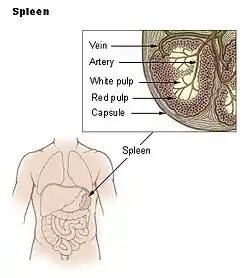

| Spleen | |

The human spleen is located in the upper left abdomen, behind the stomach | |

The spleen is an organ found in almost all vertebrates. Similar in structure to a large lymph node, it acts primarily as a blood filter. The word spleen comes from Ancient Greek σπλήν (splḗn).[1]

The spleen plays very important roles in regard to red blood cells (erythrocytes) and the immune system.[2] It removes old red blood cells and holds a reserve of blood, which can be valuable in case of hemorrhagic shock, and also recycles iron. As a part of the mononuclear phagocyte system, it metabolizes hemoglobin removed from senescent red blood cells. The globin portion of hemoglobin is degraded to its constitutive amino acids, and the heme portion is metabolized to bilirubin, which is removed in the liver.[3][4]

The spleen houses antibody-producing lymphocytes in its white pulp and monocytes which remove antibody-coated bacteria and antibody-coated blood cells by way of blood and lymph node circulation. These monocytes, upon moving to injured tissue (such as the heart after myocardial infarction), turn into dendritic cells and macrophages while promoting tissue healing.[5][6][7] The spleen is a center of activity of the mononuclear phagocyte system and is analogous to a large lymph node, as its absence causes a predisposition to certain infections.[8][4]

In humans, the spleen is purple in color and is in the left upper quadrant of the abdomen.[3][9] The surgical process to remove the spleen is known as a splenectomy.

Pulp